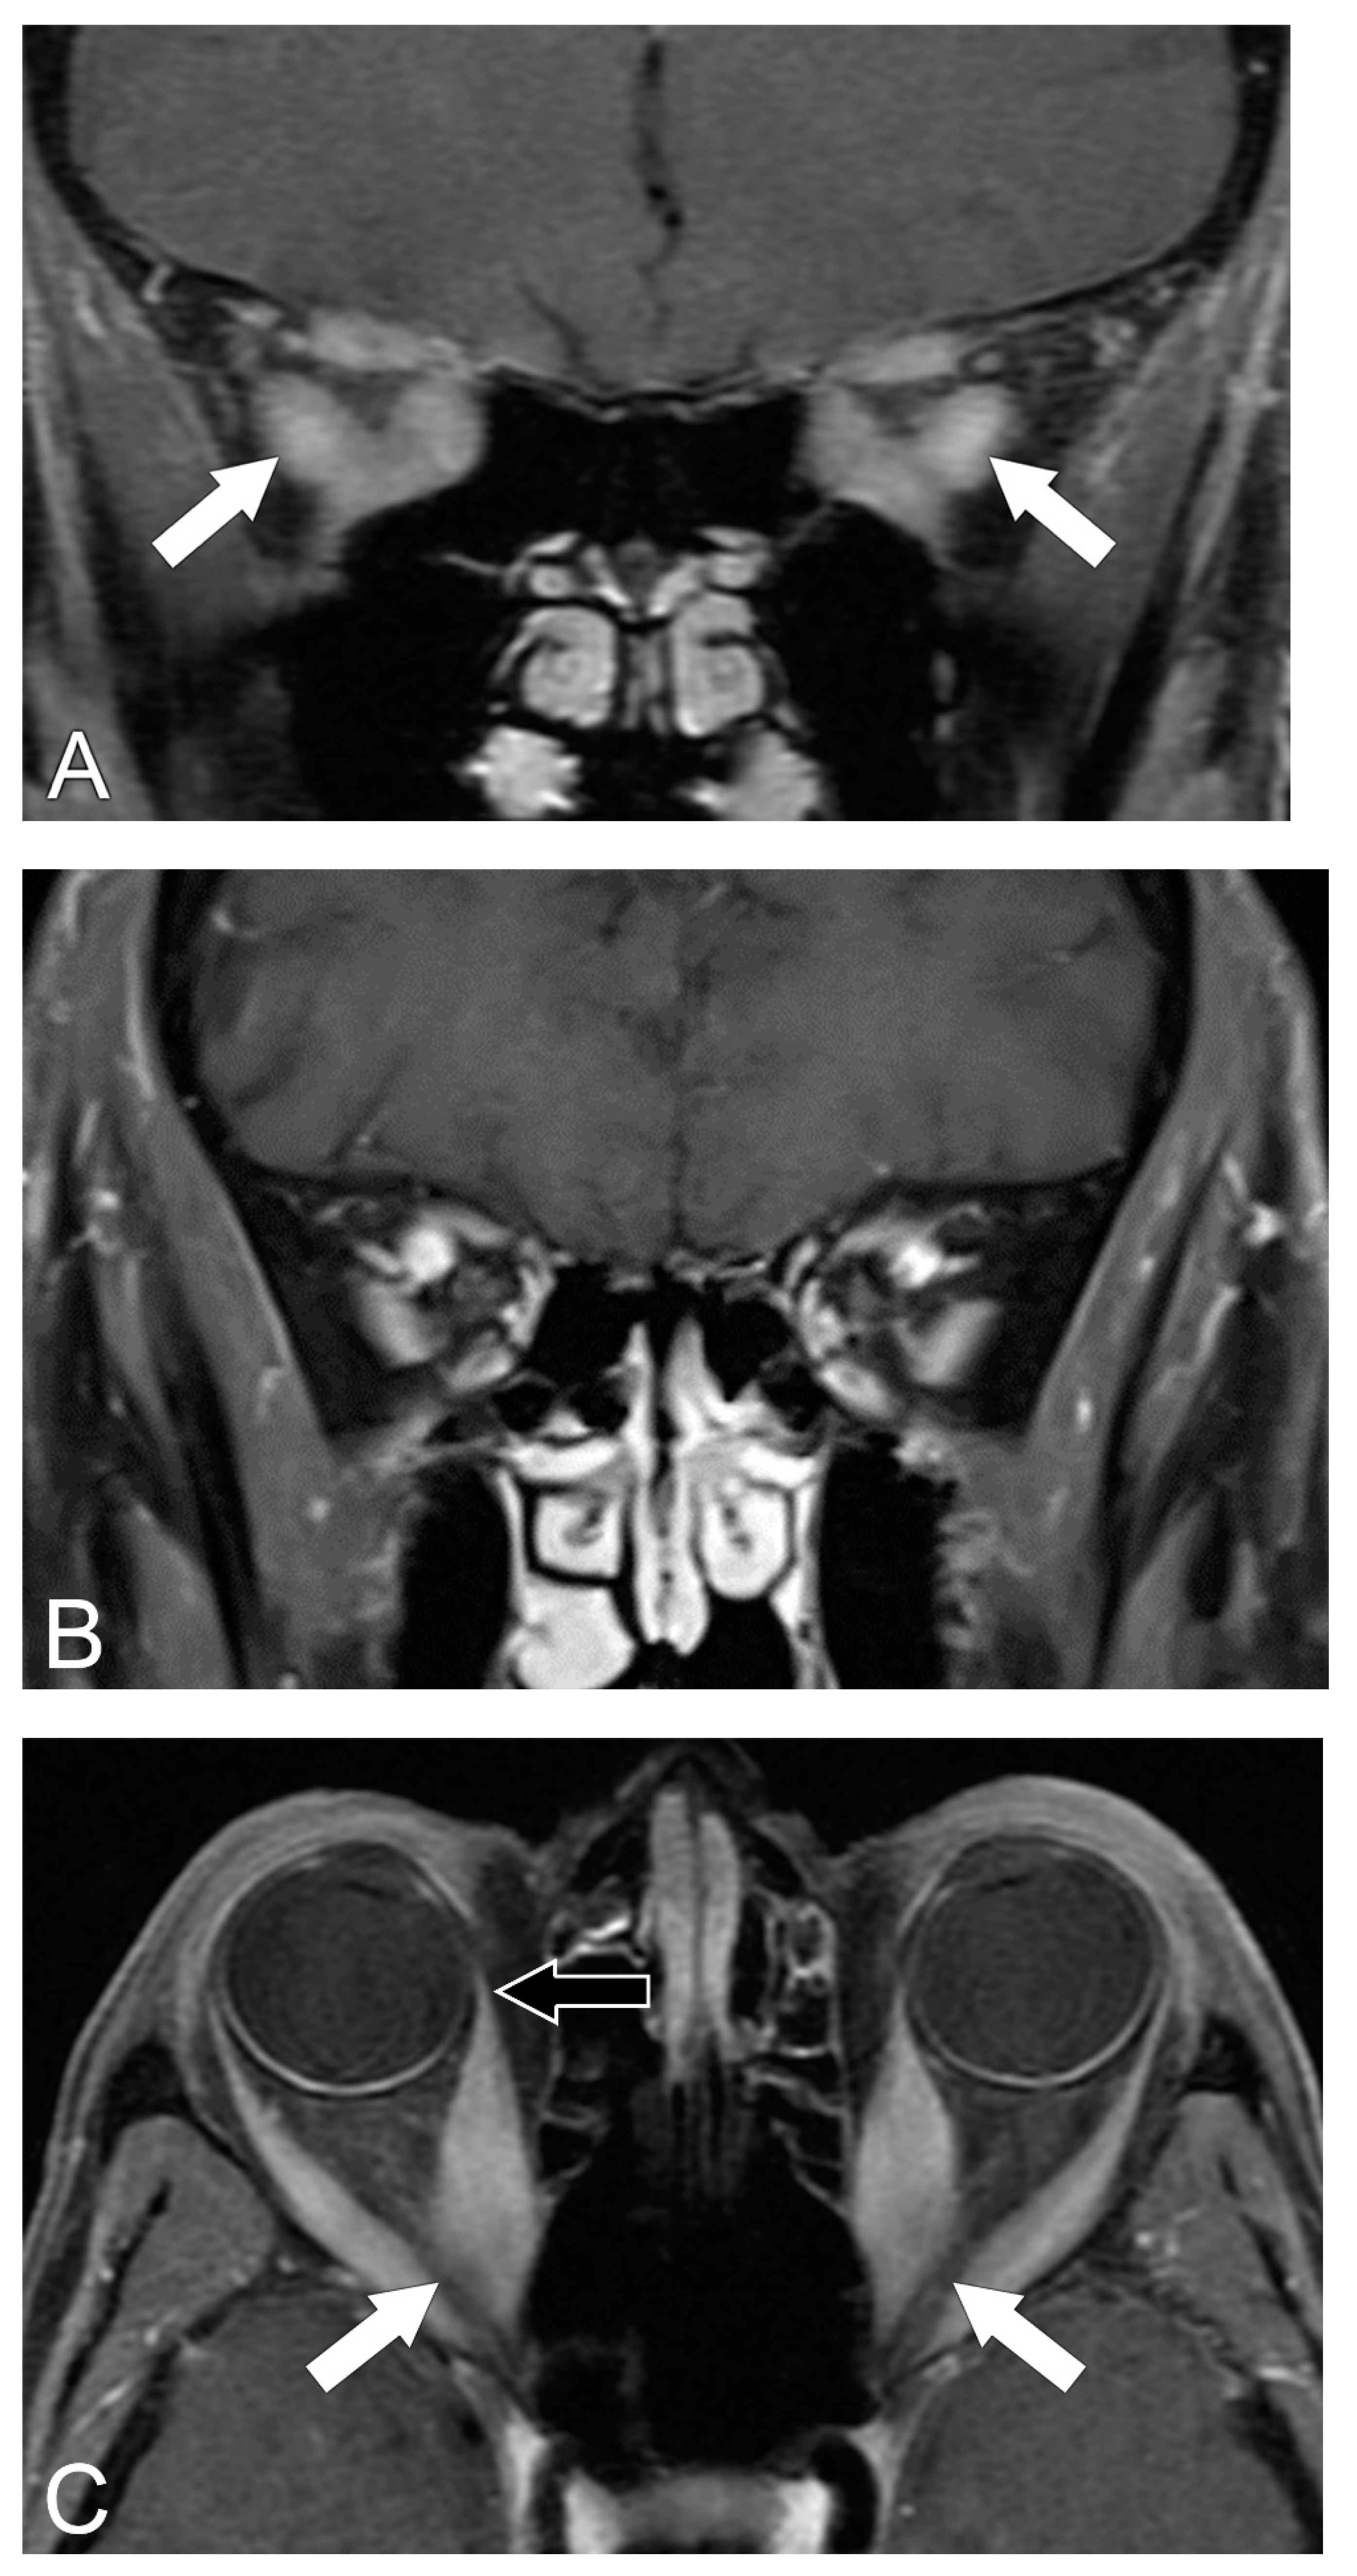

5.2. Magnetic Resonance Imaging (MRI)

5.3. MRI Correlation with Disease Severity

5.4. Diagnosis of Compressive Optic Neuropathy (CON)